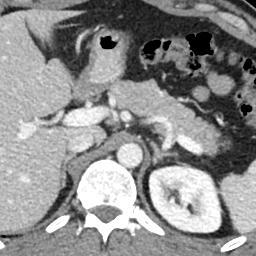

Finally, Fig. 9 displays examples of output probability maps from all of the comparative methods, i.e., HNN [12], UNet [16], PNet-MSA and “PNet-MSA+BiRNN”, where the latter one delivers the sharpest and clearest output on both CT and MRI datasets. More specifically, PNet-MSA presents results that are detailed and recover the major part of the pancreas, where both HNN and UNet suffer from significant low segmentation recall. When observing the BiRNN outputs for CT and MRI, we find detailed pancreas parts in CT have been recovered via shape continuity learning and regularization, while in MRI, the BiRNN only outputs probability map with the same shape in PNet-MSA’s output, which is optimal when the inter-slice shape changes drastically in the MRI dataset. Thus, BiRNN would help to refine pancreas segmentation with a smoothed surface in the situation that slice thickness of the 3D scans is reasonably small, e.g., <2absent2<2mm.

Refer to caption

(a)

(b)

(c)

(d)

(e)

(f)

(g)

(h)

(i)

(j)

(k)

(l)

(m)

(n)

(o)

(p)

(q)

(r)

(s)

(t)

(u)

(v)

(w)

(x)

Figure 9: Examples of output probability map: columns from left to right are the input CT/MRI image, results from HNN [12], UNET [16], the proposed PNet-MSA sub-network, and the full CNN-RNN (“PNet-MSA+BiRNN”), and the ground truth. Our model delivers the most clear probability maps which preserve detailed pancreatic boundaries.